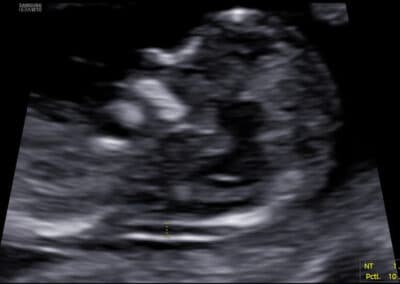

Protokol pro správné Dopplerovské vyšetření průtoku krve v ductus venosus:

CRL 45-84 mm (11-13+6 týden) Vyšetření musí být provedeno během klidové fáze (absence pohybů) plodu Zvětšení (hrudník a břicho plodu vyplňují většinu obrazovky) Mid-sagitální řez tělem plodu, barevné Dopplerovské zobrazení toku krve v pupečníkové žíle, ductus venosus a v srdci Gate 0.5-1mm přes ductus venosus (místo aliasingu – světlé barvy při Dopplerovském vyšetření) Odklon průběhu v ductus venosus 0-30º od vertikální osy Nízký filtr (50-70 Hz) Vysoká rychlost posunu křivky (2-3cm/s)